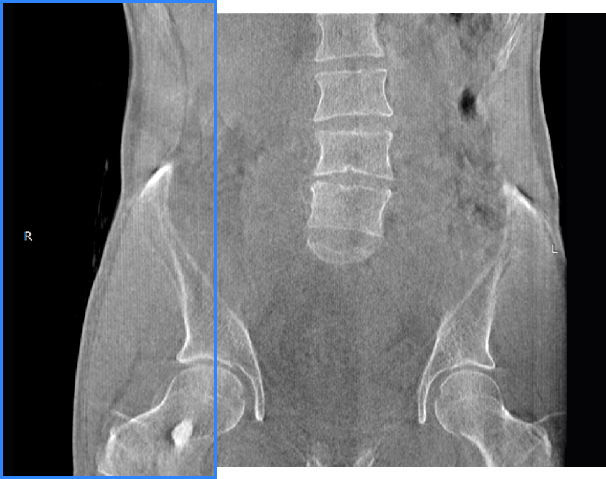

髋关节

腰椎

FOV 250mm

FOV 350mm